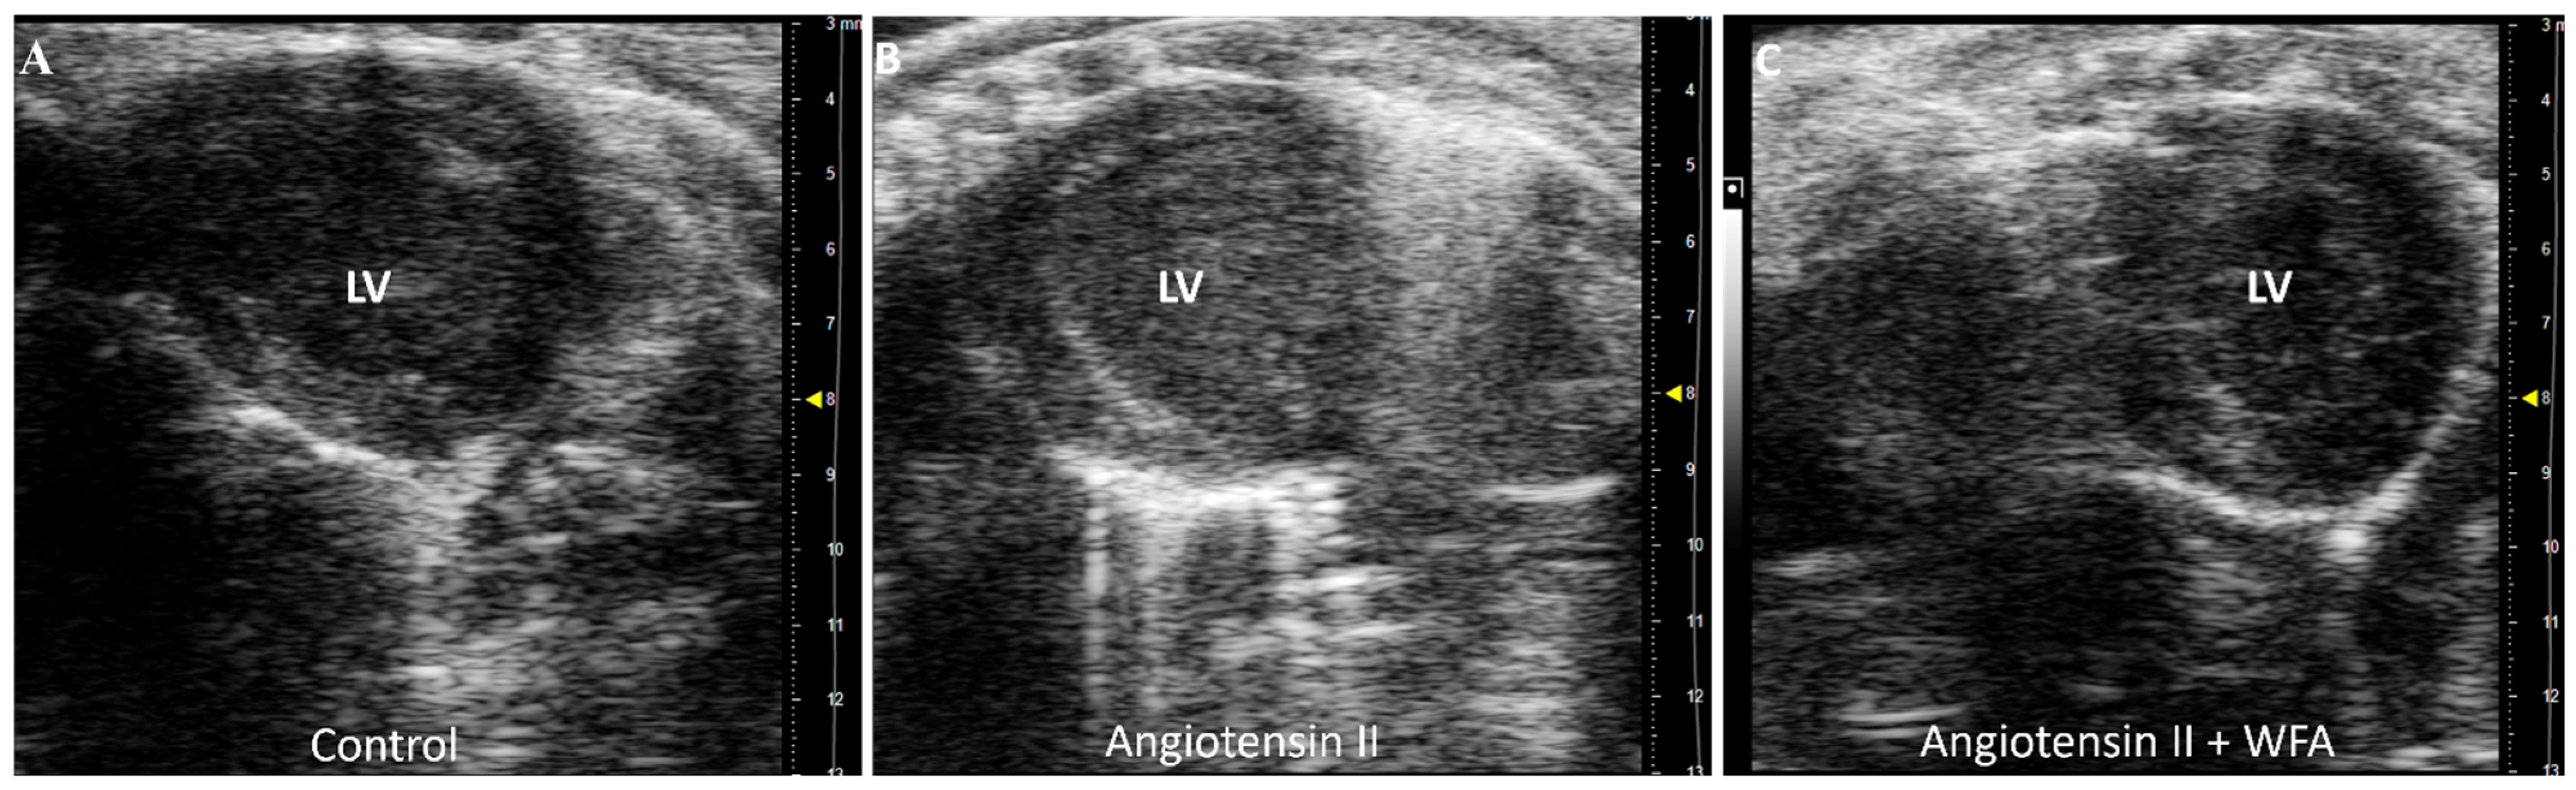

3.1. WFA Reverses LV Contractility and Systolic Function